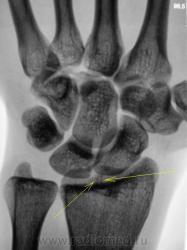

Травма. Пациент направлен на рентгенографию лучезапястного сустава. После анализа снимков - прямая и боковая, написали - "Нарушения целостности костной ткани и смещения костных отломков не выявлено". Но глаз, "зацепился" за суставную поверхность лучевой кости.

Тень есть, но вероятно это тень сосуда...

"Это" может быть тень сосуда?

Может все так травма была...но значительно ранее и все что мы видим - ее последствия. Версия тени "борозды" питающей артерии также интересна.

По мне это просто неизмененные костные трабекулы,как вариант развития.